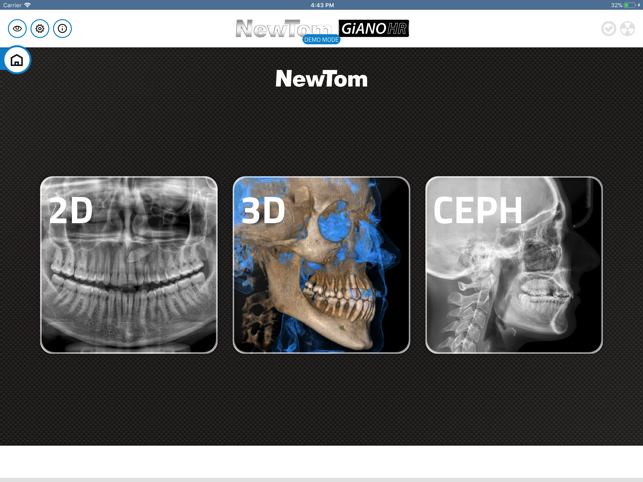

GiANO HR is a highly advanced dental equipment by NewTom, with panoramic, ceph and CBCT capabilities. NewTom Control Pad allows GiANO HR users to connect via Wi-Fi to the equipment, browse the diagnostic programs available, select an imaging modality and a region of interest before performing a radiographic examination.

NewTom Control Pad does not replace any PC workstation, where NewTom NNT imaging software will process and store the radiographic data. Nevertheless, NewTom Control Pad provides quick and easy previewing of 2D radiographs acquired, with image enhancement such as brightness, contrast and gamma correction, as well as e-mailing of 2D images to a preferred recipient.